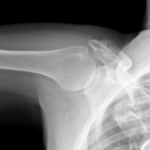

Tidigt stöd och träning är avgörande efter höft- och lårbenshalsfraktur. Foto: Shutterstock

•   Röntgenundersökning – För att se om lårbenet har gått av görs en röntgenundersökning på akutmottagningen. Är frakturen svår att se kan röntgen göras om efter någon dag eller så görs en datortomografi eller MR.